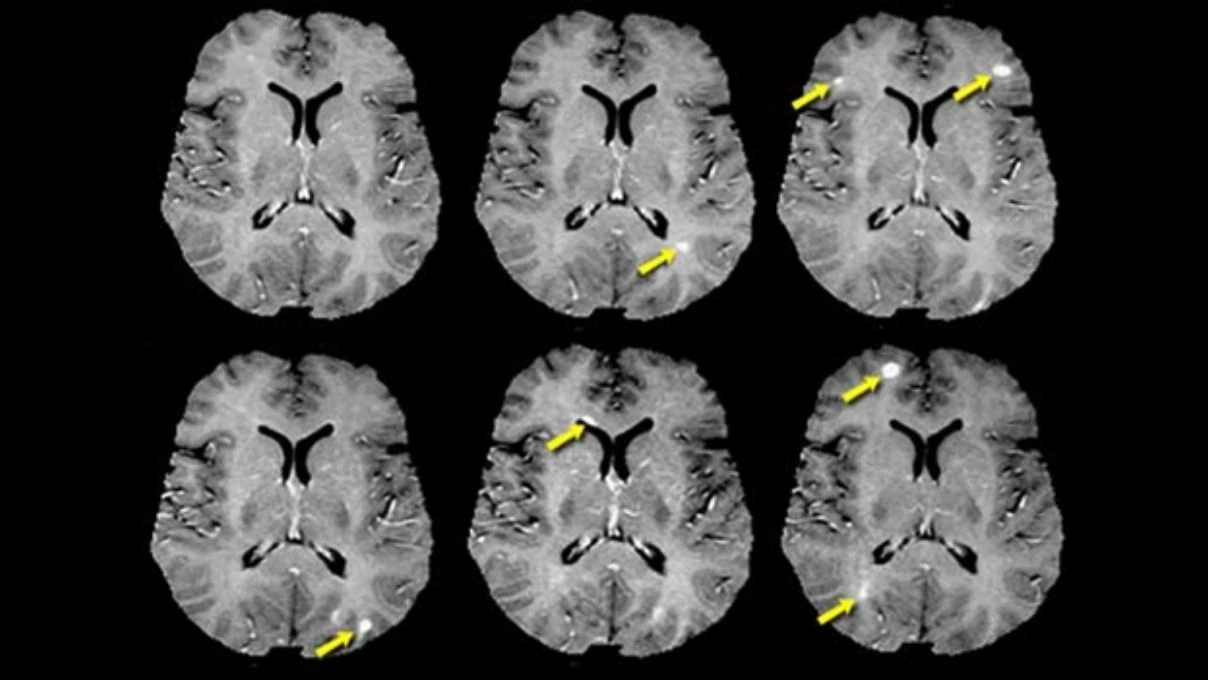

MS hastalığı, bağışıklık sisteminin sinir liflerini kaplayan koruyucu miyelin kılıfına saldırmasıyla ortaya çıkan beyin ile vücut arasındaki sinir iletiminin bozulmasıyla ortaya çıkar. Kas güçsüzlüğü, görme sorunları, yürüme, denge-koordinasyon semptomlarına neden olan merkezi sinir sisteminin oluşturduğu hastalıktır.